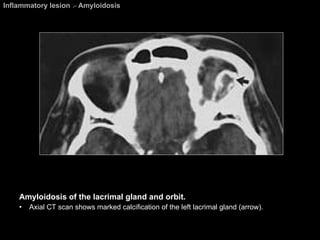

Amyloidosis On CT, amyloid deposits (homogeneous eosinophilic protein) simulate pseudotumors, vascular malformation, and other mass lesions, and the deposits can  occasionally calcify . On MR imaging, the amyloid deposits have signal intensities similar to those of skeletal muscle on all imaging sequences.

Inflammatory lesion  >  Amyloidosis Amyloidosis of the lacrimal gland and orbit.  Axial CT scan shows marked calcification of the left lacrimal gland (arrow).